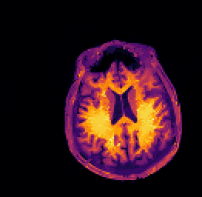

Refer to caption sinogram datafg

Refer to caption deformed ground truthfg Refer to caption deformed ground truthfg

Refer to caption side informationfg Refer to caption side informationfg

Refer to caption ground truthfg Refer to caption ground truthfg

Figure 5: PET reconstructions with structural MR side information. Filtered back-projection (FBP) and TVTV\operatorname{TV} do not correct motion and yield poor reconstructions. Both the three-step and the proposed method correct the deformation and the reconstruction satisfyingly agrees with the ground truth. We give SSIM and RD values of the reconstructed images and deformation parameters. For FBP and TVTV\operatorname{TV} no deformation was corrected and SSIM is given with respect to the deformed ground truth.

In this experiment we consider PET-MR, where we aim to reconstruct a tracer distribution using a fully sampled T1-weighted MR image of size 144×144144144144\times 144 as side information. The forward operator is modelled by a parallel beam X-ray transform with 200 angles equispaced in (0,π]0𝜋(0,\pi] and 192 bins. The sinogram data were simulated using a ground truth image deformed with respect to the side information through the rigid deformation

ϕrigid(x)=Rθx+b,subscriptitalic-ϕrigid𝑥subscript𝑅𝜃𝑥𝑏\displaystyle\phi_{\texttt{rigid}}(x)=R_{\theta}x+b, (23)

where Rθsubscript𝑅𝜃R_{\theta} is a rotation matrix (12) with angle θ=0.15.7𝜃0.1superscript5.7\theta=0.1\approx 5.7^{\circ} and b=(0.02,0.08)T𝑏superscript0.020.08𝑇b=(0.02,0.08)^{T} is a translation vector.

In this experiment we simulate data based on a dTVdTV\operatorname{dTV}-regularized reconstruction of clinical data, see [28]. The data is an instance of a Poisson random variable with parameter Ax+r𝐴𝑥𝑟Ax+r, where the background r𝑟r is chosen as constant 7 and the forward operator is scaled to about 1.31061.3superscript1061.3\cdot 10^{6} expected counts in the data. Correspondingly, the data fidelity used is the Kullback–Leibler distance (4).

The sinogram data and the deformed image which was used to generate the data are shown in the top row of Figure 5. Furthermore, we show the side information and the ground truth image. In the second row of Figure 5 we show four different reconstructions: the first one obtained through filtered back-projection, the second one utilizing TVTV\operatorname{TV} regularization, the third one using the three-step method (22), and the fourth one being the proposed method. The first two methods, which do not use the side information or correct any motion, exhibit poor image quality due to strong noise in the sinogram. On the other hand, both the three-step and the proposed method correct the deformation and the reconstructions are in very good agreement with the ground truth image.

Quantitatively, the SSIM values for filtered back-projection and TVTV\operatorname{TV} are relatively low whereas they are comparably high for both the three-step and the proposed method, with slightly better values for the proposed method. The same is also true for the relative errors of the computed deformation fields.